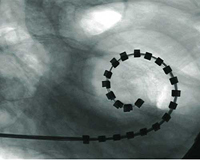

Una vez conozcamos el grado y el tipo de hipoacusia, podremos ofrecer el mejor tratamiento para cada caso; desde los drenajes transtimpánicos, hasta los tratamientos más complejos, como los implantes osteointegrados y los implantes cocleares.

La hipoacusia neurosensorial es debida a una alteración del oído interno, ya sea desde el nacimiento o de forma adquirida. En estos casos debemos recurrir a algún tipo de dispositivo electrónico como son los audífonos convencionales. Si los audífonos no son útiles, los pacientes pueden beneficiarse de dispositivos que requieren implantación quirúrgica como los implantes cocleares.